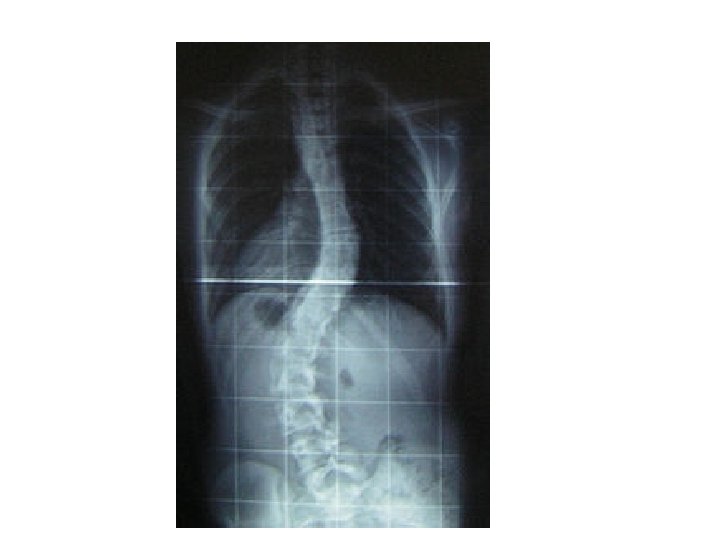

Scoliosis • Changes in muscles and ligaments on the concave side of the spinal column

Scoliosis (Cont’d) • • Pathophysiology History Treatment of children Treatment of adults